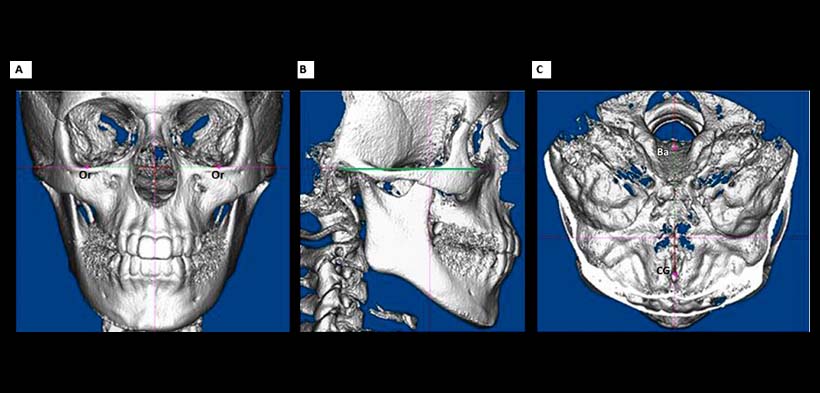

Fig. 1. Orientación de la exploración de la CBCT, que muestra las referencias anatómicas adecuadas para realizar a delimitación de la via aérea superior. (a) plano coronal; (b) plano sagital, el plano de Frankfort es indicada por la línea verde; (c) plano axial. Ba, basion; CG, crista galli; O, orbitale.